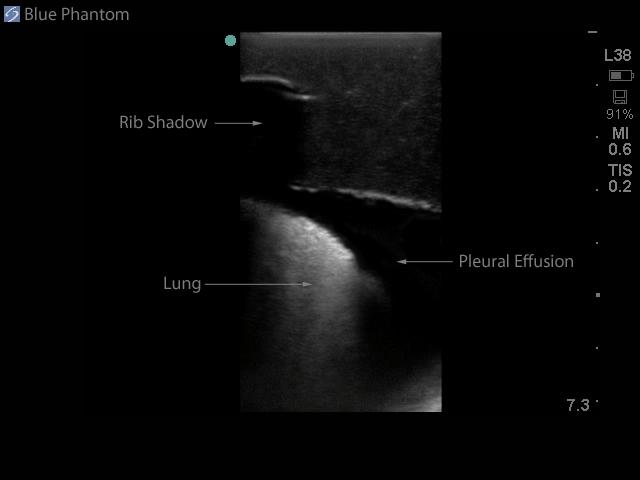

The model is of a supine adult male and extends from the upper buttocks to the lower neck. Positioned in the mid scapulary line, the ultrasound tissue insert contains chest wall superficial tissue, 6th, 7th, 8th, and 9th ribs and intercostal spaces, pleural cavity with lung and atelectatic lung, diaphragm, and superior spleen. The pleural fluid collections allow users to develop and refine their ultrasound guided thoracentesis skills. This model is extremely realistic and is self-healing offering you superb training with a low cost of ownership.

Ultrasound imaging skills include; using ultrasound system controls, transducer positioning and movement, recognition of thoracic anatomy, lung, diaphragm, anterior spleen and pleural effusions, using ultrasound to target the appropriate fluid pockets for needle guidance, and performing an ultrasound guided thoracentesis procedure. Our self-healing tissue will allow you to repeatedly perform ultrasound guided thoracentesis procedures without giving second thought to wearing out the tissue or calculating the cost per cannulation. You can expect unmatched durability from our tissue. This ultrasound training mannequin is constructed using Blue Phantom’s patented ultra-durable tissue and is extremely realistic in ultrasound imaging characteristics and feels like real human tissue. Our self-healing tissue will withstand tremendous use and will save you money by dramatically reducing the necessity for purchasing replacement parts. Constructed using Blue Phantom simulated tissue which match the acoustic characteristics of real human tissue so when you use your ultrasound system on our training models, you experience the same quality you expect from imaging patients in a clinical environment.

Blue Phantom's mid-scapular thoracentesis ultrasound training model is specifically designed for ultrasound guided thoracentesis procedures. This ultrasound training phantom aids users in developing and practicing the skills associated with a mid scapulary approach to ultrasound guided thoracentesis procedures. This model is excellent for assisting clinicians in gaining proficiency in using ultrasound to identify and guide needle and small gauge catheter insertions in a patient with pleural effusions for diagnostic and/or therapeutic purposes.The model is of a supine adult male and extends from the upper buttocks to the lower neck. Positioned in the mid scapulary line, the ultrasound tissue insert contains chest wall superficial tissue, 6th, 7th, 8th, and 9th ribs and intercostal spaces, pleural cavity with lung and atelectatic lung, diaphragm, and superior spleen. The pleural fluid collections allow users to develop and refine their ultrasound guided thoracentesis skills. This model is extremely realistic and is self-healing offering you superb training with a low cost of ownership.

Ultrasound imaging skills include; using ultrasound system controls, transducer positioning and movement, recognition of thoracic anatomy, lung, diaphragm, anterior spleen and pleural effusions, using ultrasound to target the appropriate fluid pockets for needle guidance, and performing an ultrasound guided thoracentesis procedure. Our self-healing tissue will allow you to repeatedly perform ultrasound guided thoracentesis procedures without giving second thought to wearing out the tissue or calculating the cost per cannulation. You can expect unmatched durability from our tissue. This ultrasound training mannequin is constructed using Blue Phantom’s patented ultra-durable tissue and is extremely realistic in ultrasound imaging characteristics and feels like real human tissue. Our self-healing tissue will withstand tremendous use and will save you money by dramatically reducing the necessity for purchasing replacement parts. Constructed using Blue Phantom simulated tissue which match the acoustic characteristics of real human tissue so when you use your ultrasound system on our training models, you experience the same quality you expect from imaging patients in a clinical environment.

- Ultrasound tissue module contains the chest wall superficial tissue, 6th, 7th, 8th, and 9th ribs and intercostal spaces, pleural cavity with lung and atelectatic lung, diaphragm, and superior spleen.

- Superb ultrasound imaging characteristics: extremely realistic in ultrasound imaging characteristics and feels like real human tissue

- Ultrasound tissues match the acoustic characteristics of real human tissue so when you use your ultrasound system on our training models, you experience the same quality you expect from imaging patients in a clinical environment